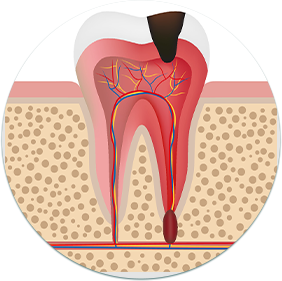

智齿蛀牙

易嵌塞食物,清洁不到位而导致龋齿发生